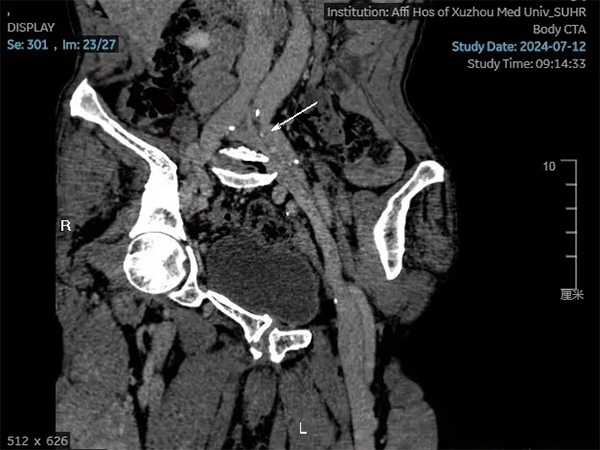

今年7月在兒子的陪同下戚大爺來到了徐州醫(yī)科大學(xué)附屬醫(yī)院介入放射科門診就診,也就是此次就診讓他的病情在30年后出現(xiàn)了轉(zhuǎn)機。在張慶橋主任的仔細詢問下,為其開具了相關(guān)檢查,下肢靜脈彩超顯示左下肢股靜脈及腘靜脈增寬伴靜脈瓣膜功能不全,CTA顯示左髂靜脈受壓。最終診斷為左髂靜脈壓迫綜合征。

圖2 左髂靜脈受壓狹窄伴管壁鈣化,遠端靜脈增寬